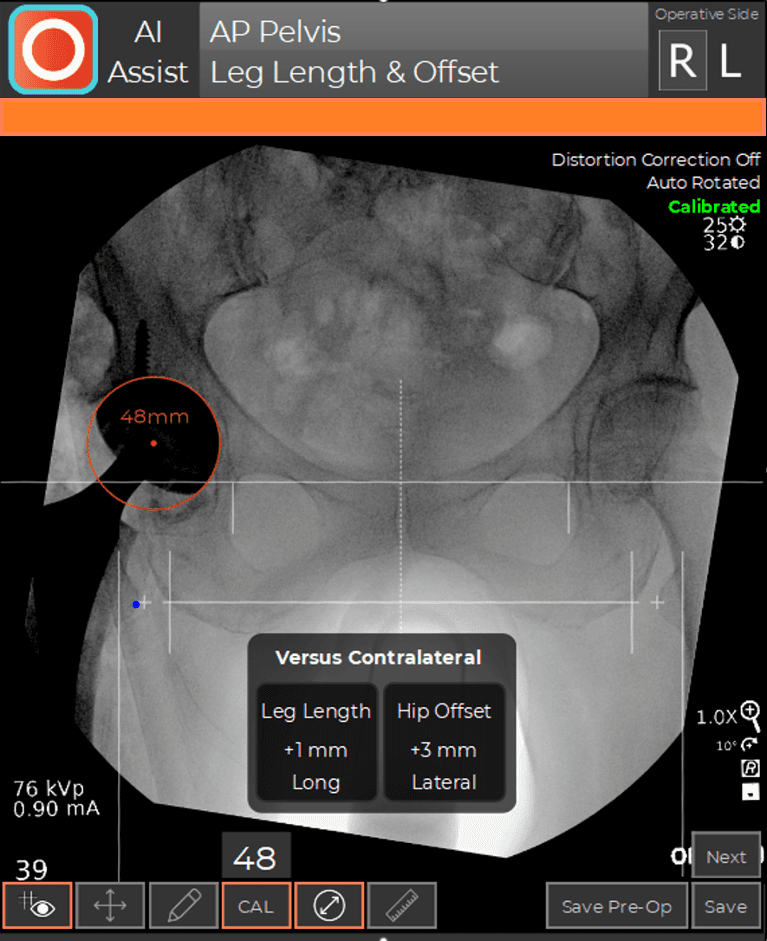

During a hip replacement using the Direct Anterior Approach, the patient is positioned supine on a traction table (the Hana® table) that allows independent positioning of the limbs during surgery. This position facilitates the use of C-arm fluoroscopy. C-arm fluoroscopy is an intra-operative x-ray camera that projects images on a computer monitor in the operating room and is used to navigate the position of the hip socket and stem in real-time during the procedure. The fluoroscopic images are analyzed by computer software (OrthoGrid Systems, Inc.), which registers multiple anatomic landmarks in order to calculate socket position, leg length, and offset. This allows the surgeon to make small adjustments intra-operatively, in order to ensure an anatomic reconstruction.